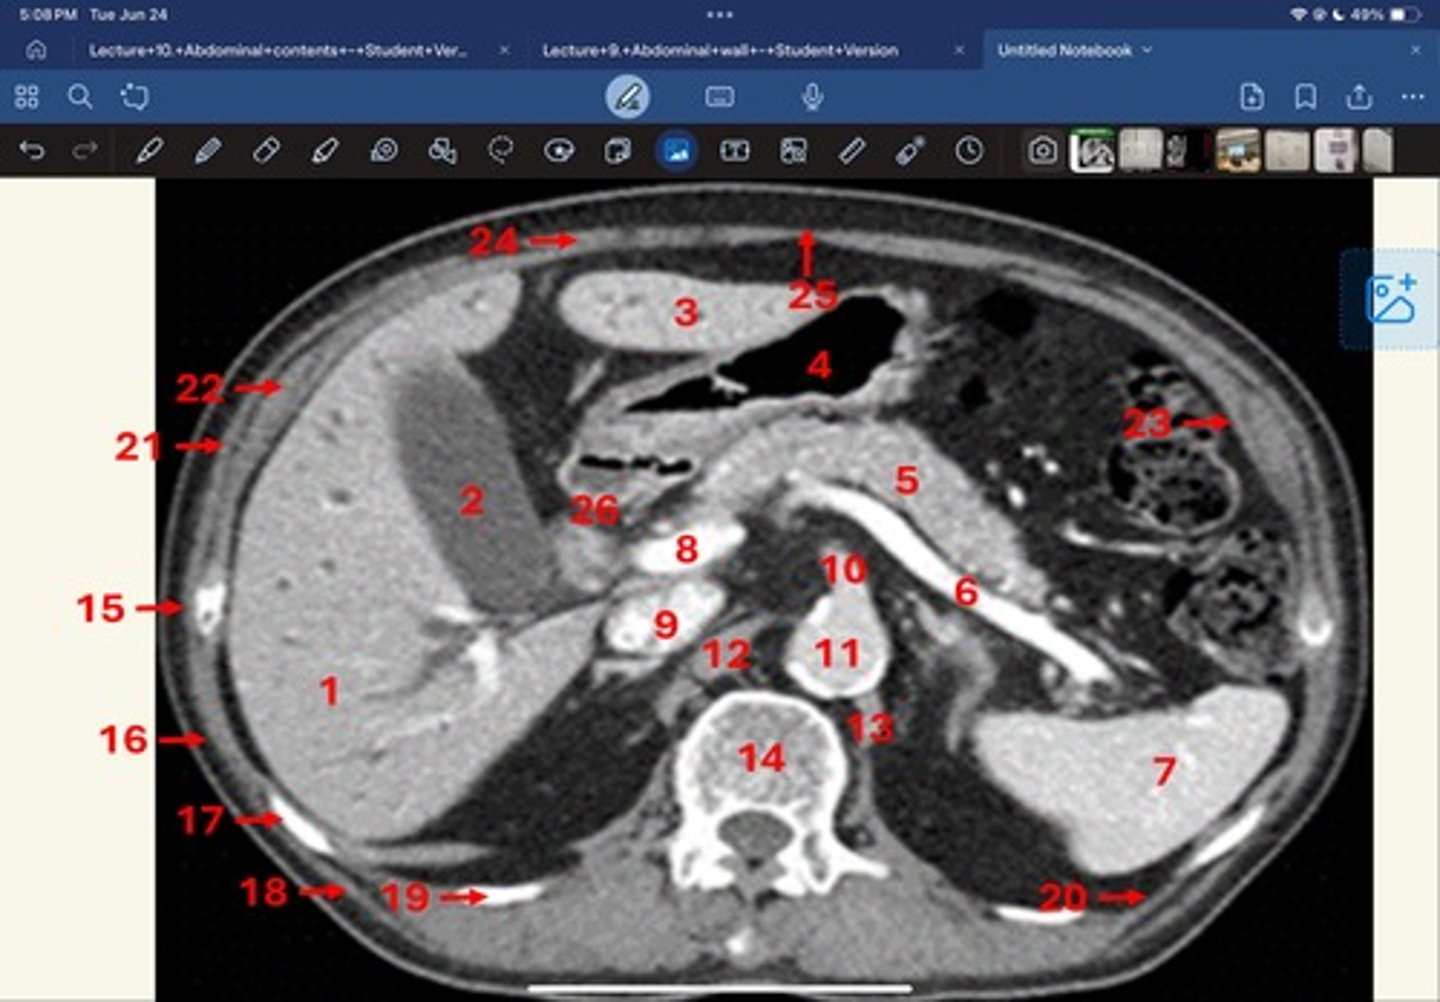

Right lobe of liver

What is 1

Gallbladder

What is 2

Left lobe of liver

What is 3

Stomach, pylorus

What is 4

Pancreas

What's 5

Splenic vein

What's 6

Spleen

What's 7

superior mesenteric vein

What's 8

Inferior vena cava

What's 9